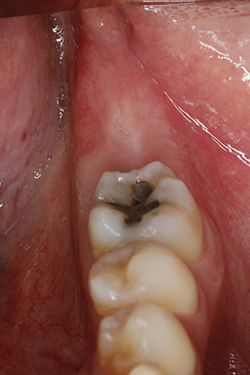

Figura 1. Fotografía intraoral. Imagen preoperatoria. Se observa el tercer cuadrante parcialmente dentado, nótese la ausencia clínica de los dientes 3.7 y 3.8

A la exploración clínica intraoral no se observaron alteraciones aparentes en suelo de boca, carrillos ni paladar blando. Los tejidos periodontales se observaron sanos y sin inflamación. Se observó ausencia de los dientes 3.6 y 3.7 (Fig. 1).